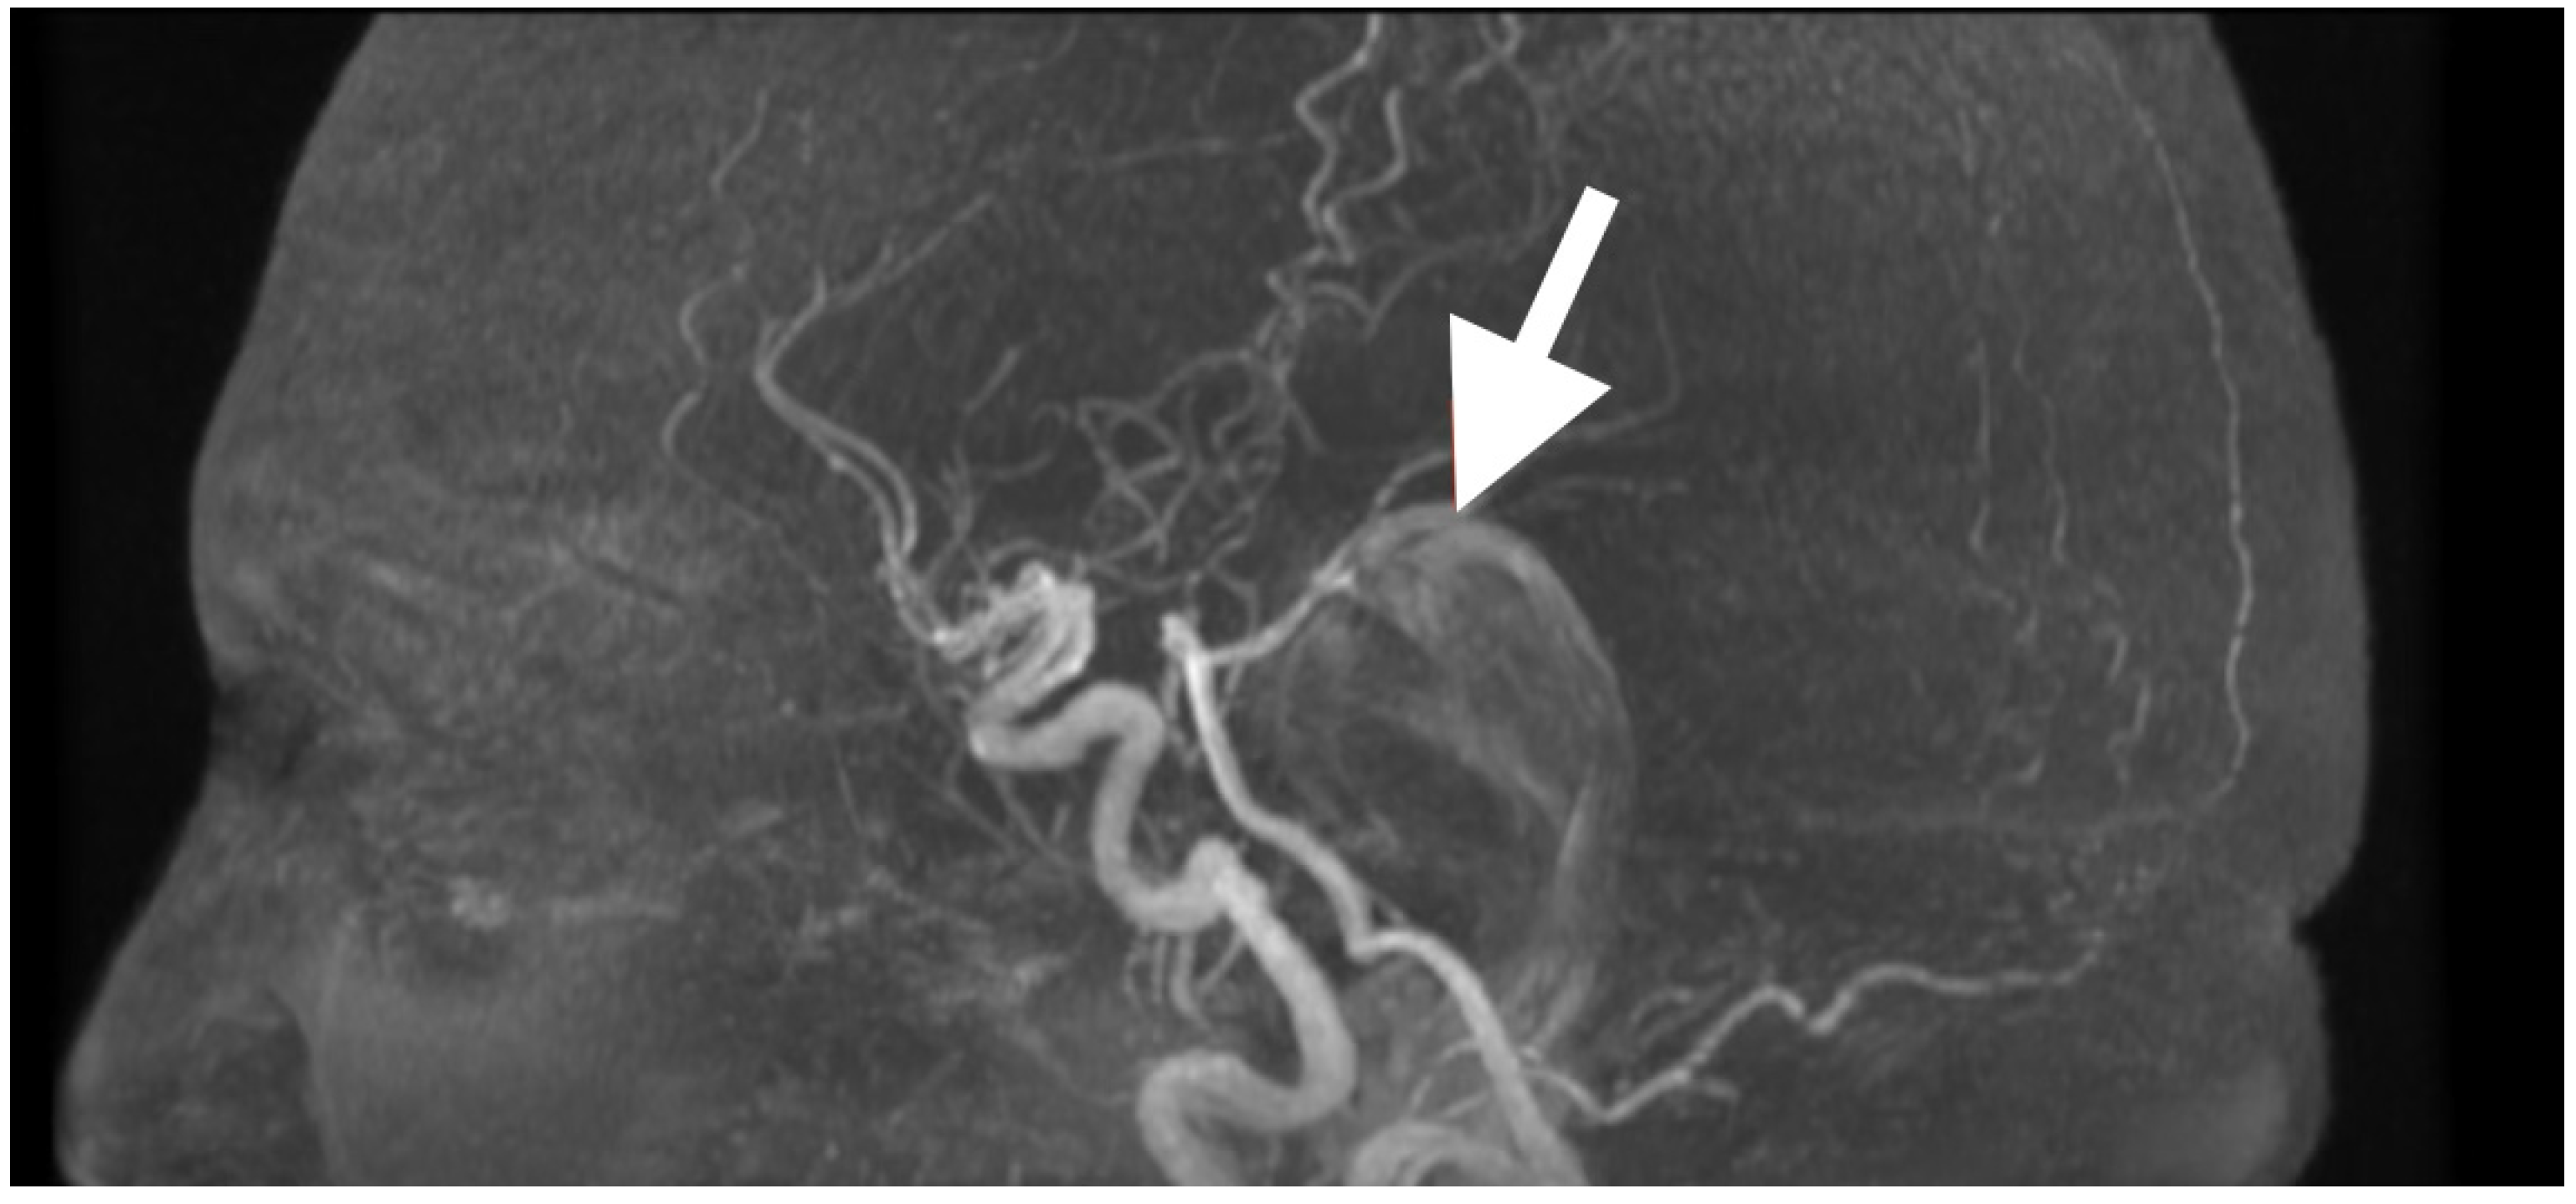

High-resolution MRI with selective MRA was obtained immediately after the examination to determine the spatial extent of the mass, vascular relationships to it, and to evaluate the current status of cerebrospinal fluid dynamics. Sagittal MRA reconstruction (Figure 1) revealed a large extra-axial mass in the left posterior fossa that centered on the cerebellar hemisphere and extended medially into the vermis. Posterior fossa arteries were lengthened and changed their course: the posterior inferior cerebellar artery (PICA) appeared to follow an elongated superior–posterior course along the dorsal surface of the mass with maintained continuity and caliber, the anterior inferior cerebellar artery (AICA), and small cerebellar perforators were also pushed to the left but appeared to be unaffected. The gradual vascular displacement without distortion, alteration, or irregularity would be consistent with chronic adaptive remodeling of the vessels; acute distortion did not occur, and there was no vascular blush, arteriovenous shunt, and/or feeding-vessel hypertrophy, identifying the extra-axial mass as an avascular, space-occupying lesion consistent with an epidermoid tumor.

Figure 1. Preoperative magnetic resonance angiography, sagittal reconstruction, demonstrating a large extra-axial mass in the left posterior fossa centered in the cerebellar hemisphere with medial extension toward the vermis. The lesion produces smooth elongation and displacement of adjacent posterior fossa arteries, most prominently the posterior inferior cerebellar artery (PICA, white arrow), which is draped over the superior–posterior surface of the mass. Vessel continuity and caliber are preserved, indicating chronic adaptive displacement rather than acute encasement or invasion. The absence of abnormal vascular blush or arteriovenous shunting supports the impression of an avascular lesion, consistent with the imaging profile of an epidermoid tumor.